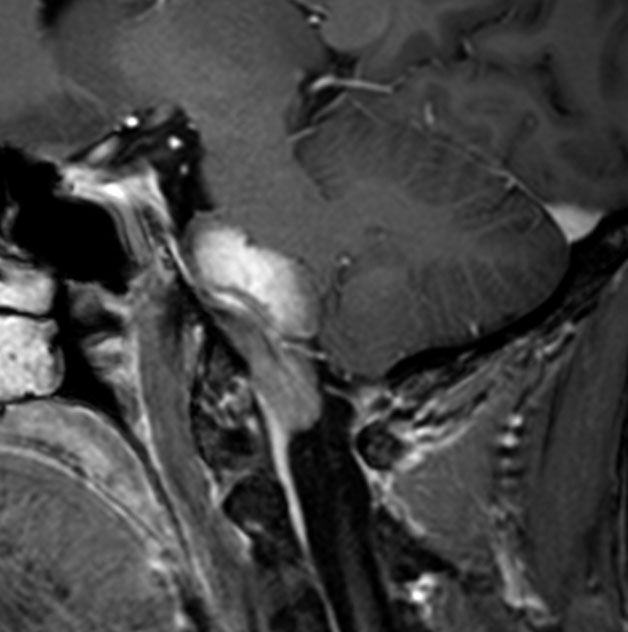

5歳の時に発見され23歳まで18年間経過観察をされてきた患者さんです。腫瘍はゆっくり,しかし確実に増大して,手術前には頭痛がひどく薬も効かず歩けなくなったという症状でした。術後に頭痛が無くなったので,のう胞による症状だったのでしょう。

下垂体柄の周囲にのう胞性腫瘍があります。T1強調画像では等信号,T2強調画像ではまだらな信号になっています。23年という長い経過から液状内容物が固形化したものと推定されます。T2で低信号となる部分があるのですが,黄色肉芽腫とは異なる像です。

下垂体柄は長く伸びています。のう胞による長期の圧迫のため斜台上部がerosionになって凹んでいます。トルコ鞍内の中間葉の位置に典型的な小さなラトケのう胞(黄色矢印)がみられますが,これは長年変化していませんでした。

左前頭側頭開頭 pterional approachで,のう胞壁を含めて完全摘出 complete removalしました。のう胞は下垂体柄の左側に付着してそこから発生したものでした。内容物は固体で寒天状のコロイドでした,一部軟らかくて一部は線維化していました。のう胞壁は半透明で薄い部分も線維性の膜状の部分もありました。病理検査では上皮細胞が証明されて内胚葉のう胞 endodermal cystの診断です。

ラトケのう胞はhiatusから内容液吸引だけして,皮膜はもちろんそのままにしています。